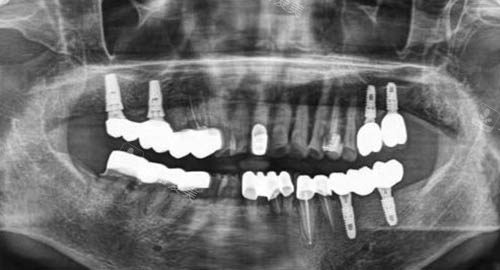

多颗牙齿种植ct

在技术层面,榆林中诺口腔医院以“智能化诊疗”为特色,引入一系列较高设备与智能化技术,让口腔治疗更更准一些、更较高的效率。

例如,医院配备进口CBCT三维影像系统,可清晰呈现牙齿、牙槽骨、神经等结构,为种植、矫正等项目提供更准一些数据支持;口内扫描仪取代传统印模,3分钟即可完成口腔数据采集,避免恶心不适,且模型精度更高;种植手术中采用3D导板技术,实现“更准一些导航种植”,减少创伤、缩短手术时间;矫正项目则通过智能化方案设计,让患者提前看到矫正结果,提升治疗信心。